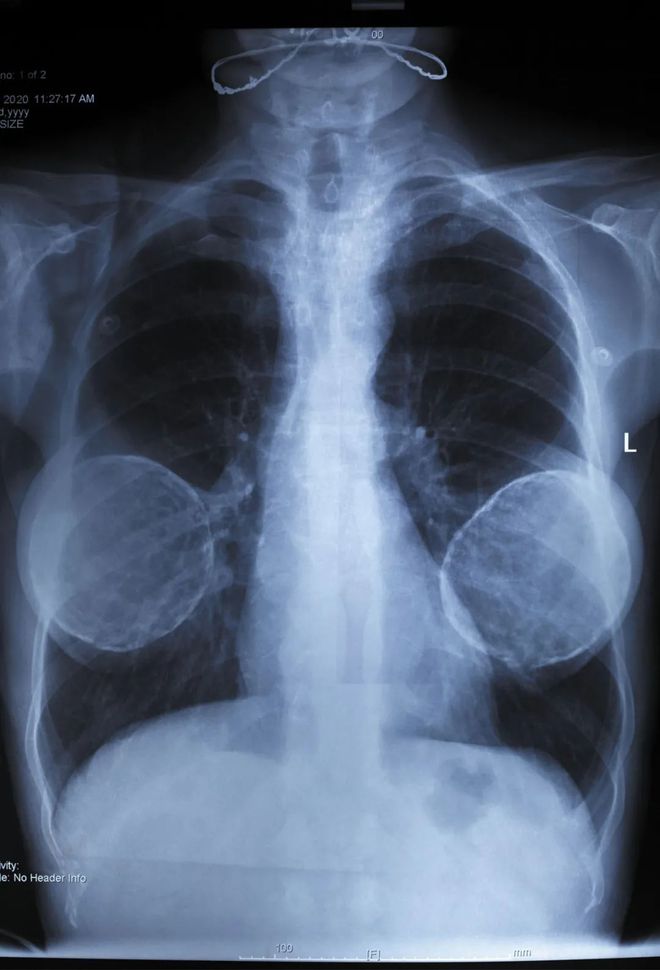

在支付了約540,000元人民幣(約合74,600美元)的手術費用后,該女子最初看到了積極的結果。然而,隨著時間的流逝,她的乳房出現了不對稱和疼痛。隨后的體檢顯示異物植入。

兩家醫院的進一步檢查證實,植入物不是自體組織,而是含有動物源性蛋白質的合成材料,包括駱駝、蝙蝠和黑猩猩的蛋白質。出于安全原因,這名婦女接受了手術,以移除植入物并重建乳房。

該 a , 油性 約 200 , 它 與 . , 有些 可能 , 風險。

外科醫生取出了一種黃色的軟膏狀物質,總計約200毫升,并用假肢代替。但是,可能仍存在一些殘留物,這些殘留物會構成潛在的健康風險。